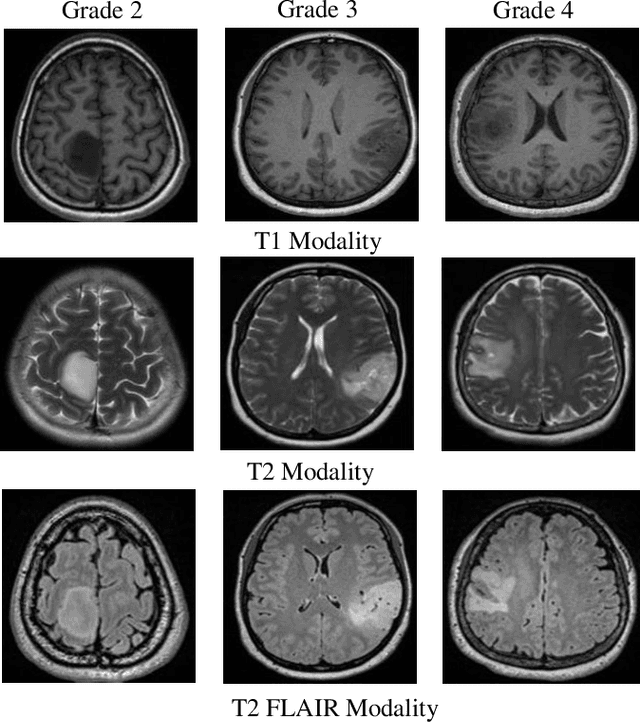

Abstract:Medical image analysis frequently encounters data scarcity challenges. Transfer learning has been effective in addressing this issue while conserving computational resources. The recent advent of foundational models like the DINOv2, which uses the vision transformer architecture, has opened new opportunities in the field and gathered significant interest. However, DINOv2's performance on clinical data still needs to be verified. In this paper, we performed a glioma grading task using three clinical modalities of brain MRI data. We compared the performance of various pre-trained deep learning models, including those based on ImageNet and DINOv2, in a transfer learning context. Our focus was on understanding the impact of the freezing mechanism on performance. We also validated our findings on three other types of public datasets: chest radiography, fundus radiography, and dermoscopy. Our findings indicate that in our clinical dataset, DINOv2's performance was not as strong as ImageNet-based pre-trained models, whereas in public datasets, DINOv2 generally outperformed other models, especially when using the frozen mechanism. Similar performance was observed with various sizes of DINOv2 models across different tasks. In summary, DINOv2 is viable for medical image classification tasks, particularly with data resembling natural images. However, its effectiveness may vary with data that significantly differs from natural images such as MRI. In addition, employing smaller versions of the model can be adequate for medical task, offering resource-saving benefits. Our codes are available at https://github.com/GuanghuiFU/medical_DINOv2_eval.